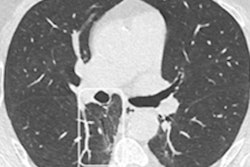

Another area receiving significant attention in the past year is the development of AI algorithms to help evaluate cystic fibrosis on CT imaging in children. The disease may lend itself to AI algorithms, given there are easily recognized CT biomarkers that show progression or decline of symptoms such as bronchiectasis, peribronchial thickening, bronchial mucus, and others in patients undergoing treatment, Schalekamp said.

French researchers from the University of Bordeaux and U.S. colleagues at the University of Cincinnati in Ohio developed one such algorithm based on a dataset of images from patients with cystic fibrosis between the ages of 4 and 54.

"They were able to demonstrate that patients on treatment on follow-up CTs had lower amounts of these biomarkers, which was easily picked up by this AI system," Schalekamp said.